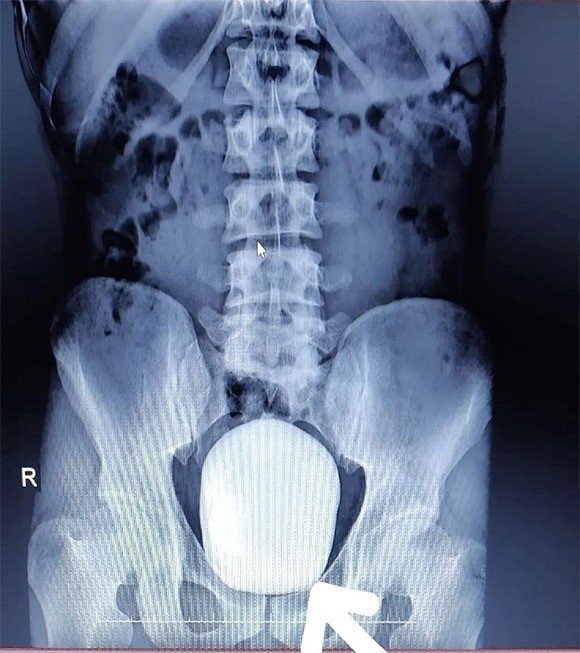

Karaman'da ikamet eden 27 yaşındaki Barış Yıldız isimli hasta idrar yaparken yanma şikayeti ile Karaman Eğitim ve Araştırma Hastanesine başvurdu. Çekilen röntgeninde hastanın mesanesinde 2 adet büyük çapta taş tespit edildi. Doç. Dr. Güven Erbay ve Dr. Öğretim Üyesi Ahmet Şanlı tarafından yapılan cerrahi operasyonla hastanın mesanesindeki 2 taş başarılı bir şekilde alındı.

Başarılı geçen ameliyatla ilgili değerlendirmelerde bulunan Doç. Dr. Güven Erbay, "Hastanemize idrarda yanma şikayeti ile başvurdu. Yapılan tetkik ve görüntüleme sonucunda mesanesinde devasa bir taş olduğu gördük. Bunun üzerine ameliyat kararı aldık ve açık ameliyatla bu taşı aldık. Normalde mesane taşı yaşlı hastalarda ve prostatı olanlarda oluşur. Genç yaştakilerde pek beklediğimiz bir durum değildir. Başarılı geçen ameliyatın sonunda hastamızın mesanesinden 15 ve 5 santim boyutunda 2 tane taş çıkardık. Hastamızın sağlığı gayet iyi durumdadır. Şu ana kadar bilinen ve bizim de bildiğimiz kadarıyla bir hastadan çıkarılan taş bin 900 gram ağırlığındaydı. Bizim çıkardığımız 2 taşın ağırlığını ölçtüğümüzde bin 50 gram geldi. Bizim bildiğimiz üzere bu çıkarılan taşın Türkiye sınırlarında şimdiye kadar mesaneden çıkarılan en büyük taş olduğunu düşünmekteyiz" dedi.